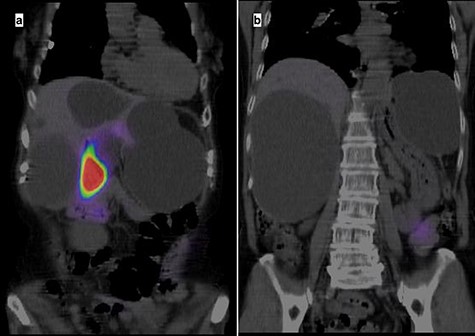

A 74-year-old woman presented with right upper abdominal pain and poor dietary intake. She had no notable medical history or history of abdominal trauma. Abdominal computed tomography (CT) showed multiple liver cysts, with the size of the largest cyst in the right lobe measuring 155 × 113 × 106 mm (Fig. 1a). In addition, a large cyst measuring 135 mm in the left lateral lobe strongly compressed the stomach (Fig. 1b). T1-weighted magnetic resonance imaging revealed different findings in the right and left lobe cysts, and there were no enhanced structures in the liver cysts (Fig. 2). Positron emission tomography-CT did not show increased 18F-fluorodeoxyglucose metabolism in any of the liver cysts (Fig. 3). Moreover, hepatobiliary scintigraphy with CT showed no biliary communication with the liver cysts (Fig. 4). The patient was diagnosed with symptomatic and multiple liver cysts with no biliary communication or malignancy. Therefore, LF was performed.

Positron emission tomography-CT showing no increase in 18F-fluorodeoxyglucose metabolism in the liver cysts.